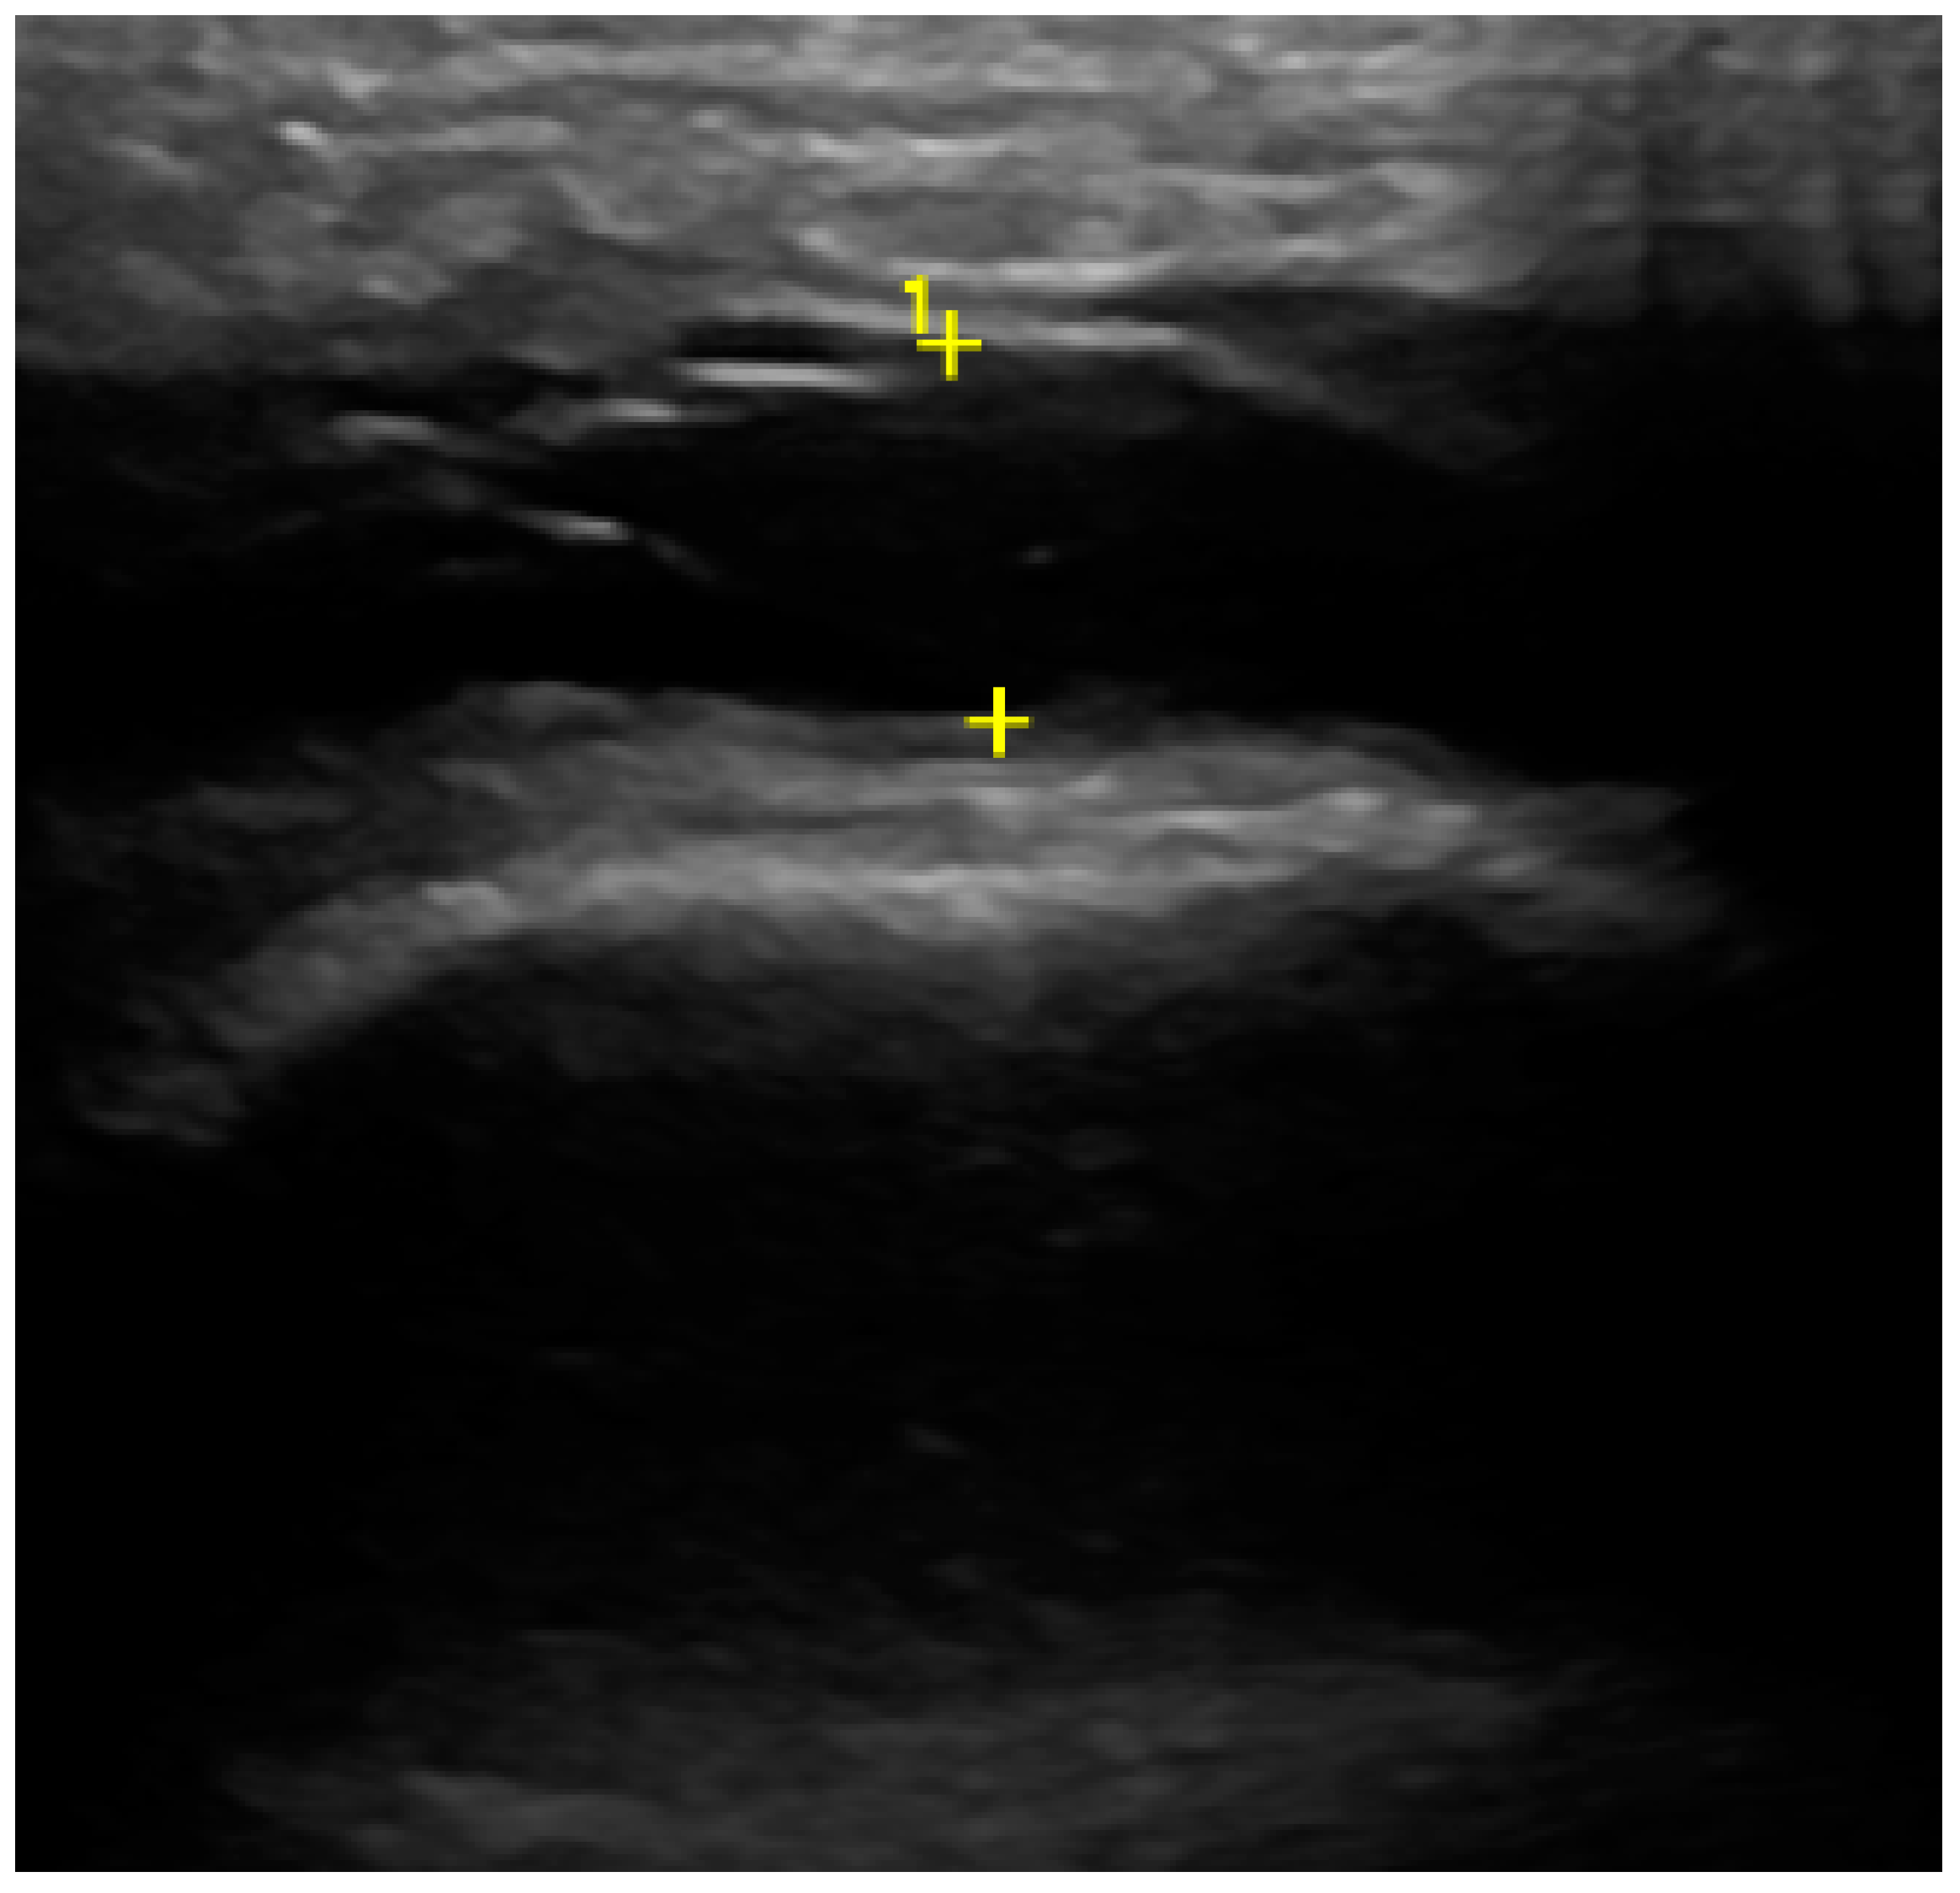

In the US analysis, we aimed to assess synovial effusion within the joint, which is indicative of inflammation or pathological fluid accumulation (Figure 2). Additionally, a thorough examination of the osseous structures was conducted. This included identifying the presence of osteophytes and evaluating any erosive changes to the bone surfaces. Furthermore, the analysis extended to the evaluation of the articular disc (Figure 3). For the purposes of the study, a unique research protocol was proposed, consisting of the assessment of the temporomandibular joint in the neutral position (mouth closed) with the mouth in maximum opening and the assessment of the path of the articular disc movement in a dynamic test. All examinations were performed by the same experienced radiologist using a LOGIQ E10 ultrasound with a dedicated L8-18i hockey stick linear probe (GE Healthcare, Boston, MA, USA).

Figure 2. Ultrasound (effusion within the joint).